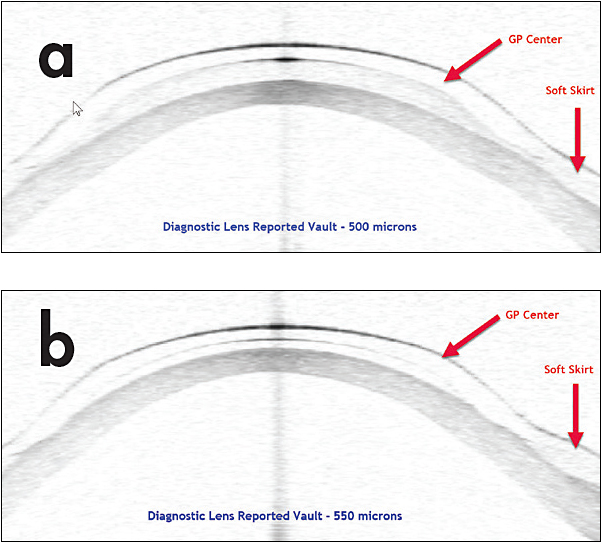

From www.clspectrum.com

Anterior SegmentOCT Improves Specialty Contact Lens Fitting Experience Lens Vault Definition Lens vault was defined as the perpendicular distance between the anterior pole of the crystalline lens and the horizontal line joining the 2 scleral spurs on horizontal as. Lens vault was defined as the perpendicular distance between the anterior pole of the crystalline lens and the horizontal line joining. To measure lens vault (lv) and to assess its correlation with. Lens Vault Definition.

From www.reviewofcontactlenses.com